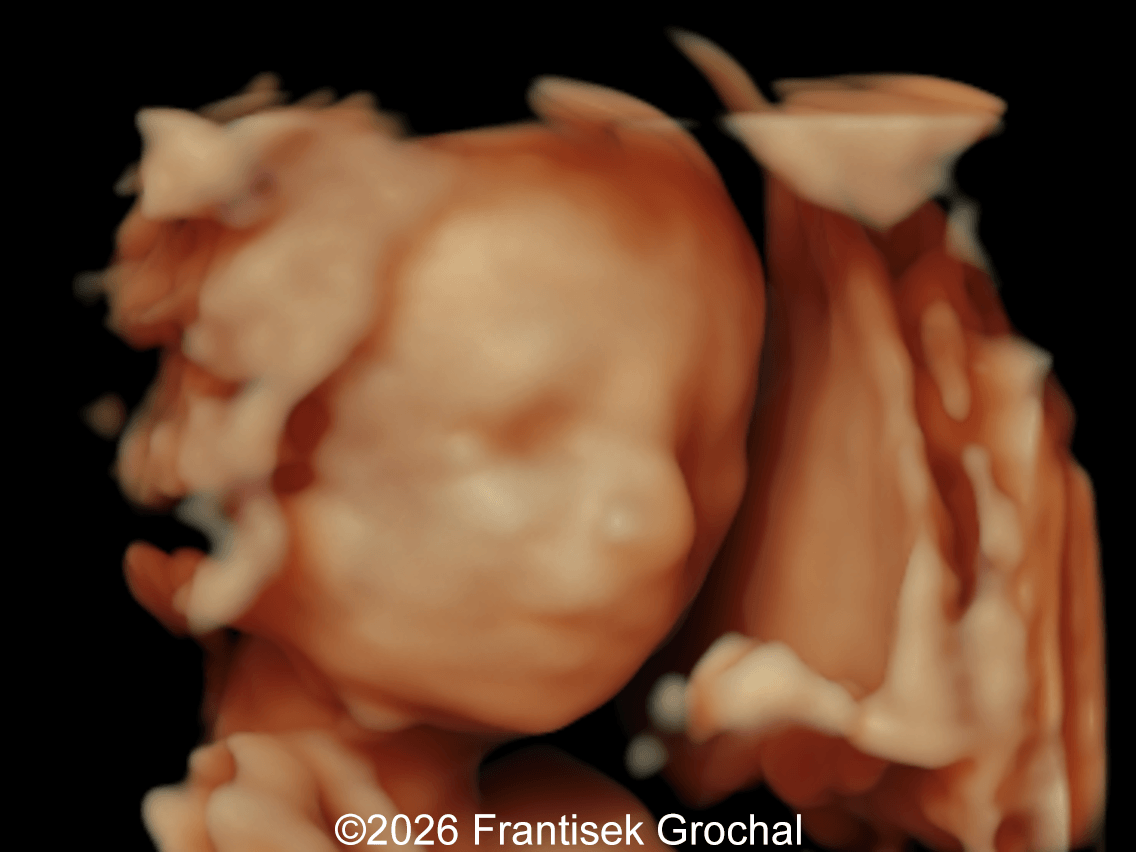

19+4 weeks of gestation; sagittal view of the fetal head demonstrating prefrontal edema, nasal bone hypoplasia, retrognathia, and a short corpus callosum.

Image 1 19+4 weeks of gestation; sagittal view of the fetal head demonstrating prefrontal edema, nasal bone hypoplasia, retrognathia, and a short corpus callosum.